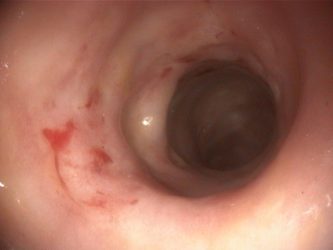

Bulldog Francés, macho entero de 8 años, que acude por diarrea crónica de intestino grueso. Presenta heces mucosas con hematoquecia y tenesmo, sin pérdida de peso asociada, de seis meses de duración. En el examen físico general y en las analíticas completas no se detectan alteraciones destacables. Se realiza un coprológico con resultado negativo. La ecografía abdominal revela un engrosamiento marcado y difuso de la pared del colon, sin pérdida de estratificación. En la colonoscopia se aprecia la mucosa del colon marcadamente engrosada e irregular (Figura 4). El estudio histopatológico finalmente es compatible con una colitis granulomatosa.

El agente infeccioso más probable implicado en las colitis granulomatosas es Escherichia coli invasiva. Las razas más predispuestas son el Bulldog Francés y el Bóxer. La confirmación se realiza mediante tinción inmunohistoquímica, hibridación in situ o PCR específica en biopsias para detectar E. coli en macrófagos de la mucosa colónica. El tratamiento de elección es enrofloxacino durante 6–8 semanas, evaluando la respuesta clínica y repitiendo la colonoscopia o la biopsia si es necesario. Se recomienda realizar un cultivo de mucosa colónica, dado que se han descrito recientemente cepas resistentes a las fluoroquinolonas.